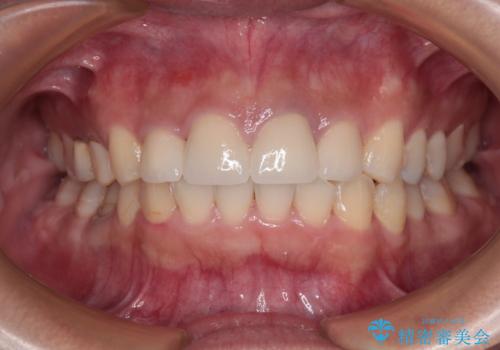

外に飛び出して磨きにくい奥歯と上下前歯の隙間 インビザラインによる矯正治療

- 上下前歯の隙間と、外側を向いていて歯磨きのしにくい奥歯を気にして来院された患者様です。

下顎前歯が1本欠損しており、上下アーチはアンバランスとなりますが、インビザラインを用いて上下の隙間を改善しながら歯列を整えることとしました。

下顎前歯の1本欠損により左右の咬合が不安定となり、治療経過で噛みにくい状態が続きましたが、最終的には違和感なく噛めるようになりました。